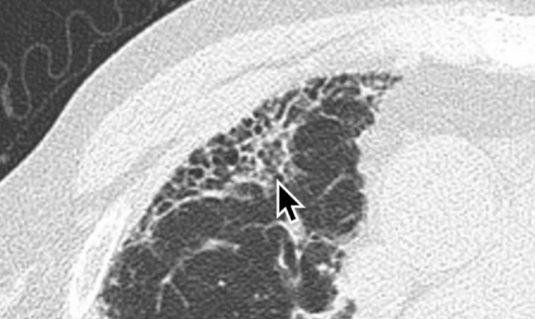

Rayon de miel

honey honeycombing rayondemiel emphysème emphyseme